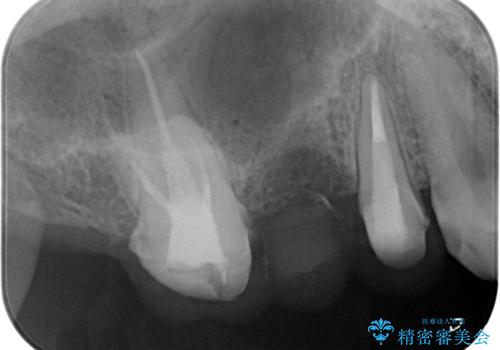

- 「奥歯のクラウンが取れてしまったので診てほしい。」とセラミック治療を希望され来院されました。

診査を行ったところ、クラウンの取れた歯は、割れてしまっており再度クラウン装着が難しい状況でした。

抜歯を行ったのち、ブリッジ製作を行うことで咬合機能の回復を計画します。